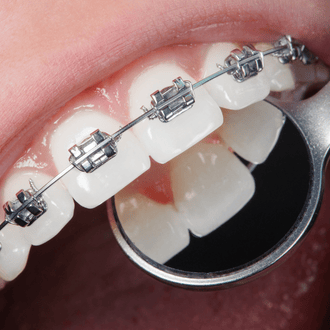

We maintain strict hygiene standards, use modern dental equipment, and follow proven clinical procedures for accurate diagnosis and long-lasting results. From routine check-ups to advanced dental treatments, our clinic is fully equipped to deliver complete oral health solutions under one roof.